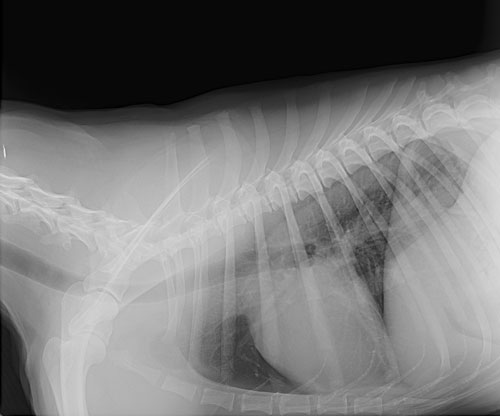

Our in house radiography service allows us to quickly diagnose certain disorders. We are also able to refer special cases to experts in order to pet assist your pet.